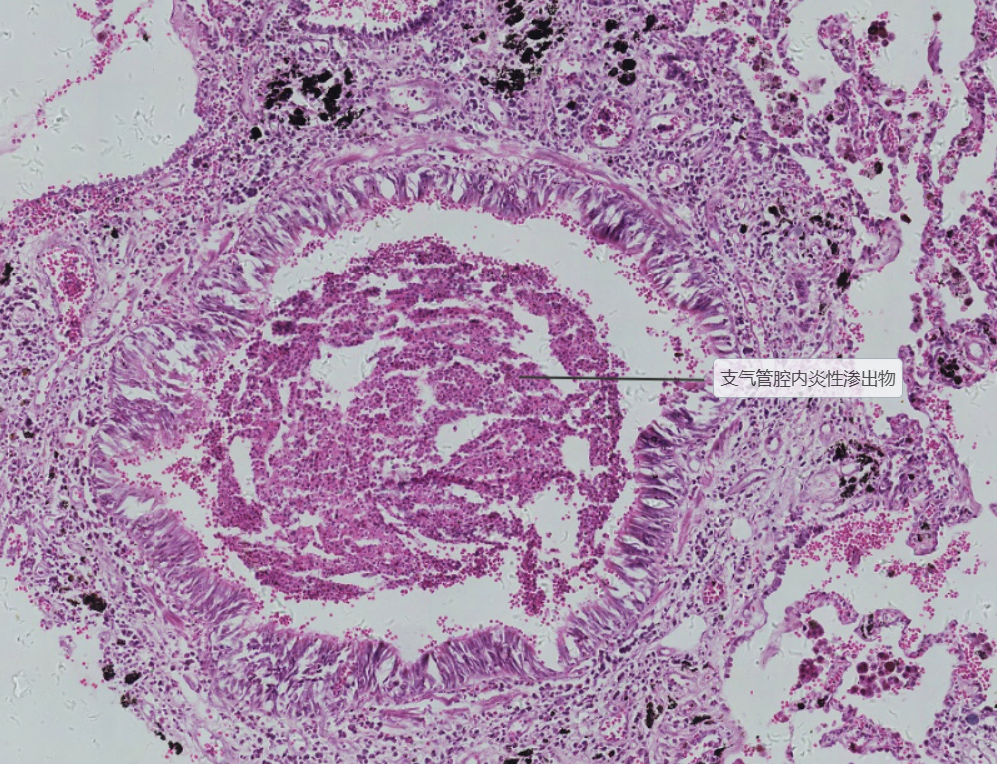

3 小叶性肺炎